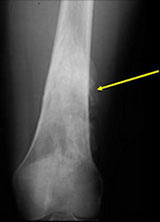

Radiology

X-Rays:

- Lobulated and ossified exophytic mass (cauliflower-like) adjacent to the cortex; attached to metaphyseal cortex via a broad base

- Centrally, the tumor is radiodense (demonstrates ossification)

- Peripherally there may be small radiolucies that represent low grade cartilaginous lobules, fibrous tissue or fat

- The underlying cortex may be thickened

- There is no periosteal reaction since the tumor comes from the outer layer of the periosteum and therefore does not elevate the periosteum.

- Large tumors encircle the bone

- Appears to have broad attachment to underlying cortex with a cleft between exophytic base and cortex at periphery. This is referred to as a “String Sign” (cleft is often only identifiable on CT scan)

- There may be invasion of the medullary canal with long standing disease

- High grade or defifferentiated areas may appear as large radiolucent areas/mass adjacent to radiodense areas